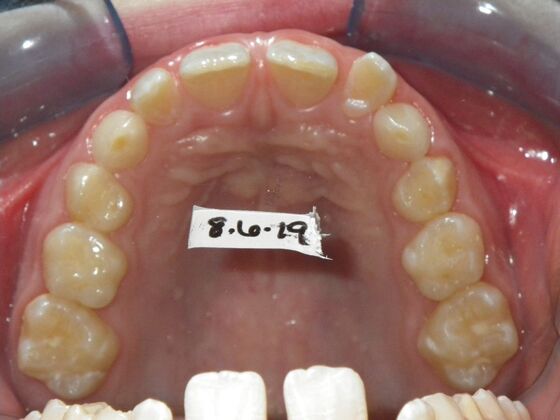

Orthodontic treatment in Phases: Case 12

This patient does not like his anterior deep bite and the flaring of the right lateral incisor as well as anterior spacing. The solution was to correct his Class II molar relationship, Division II and deep anterior bite and close spacing as much as possible with addition of composite restorations on distals of lateral incisors. We began with utility archwires, eventually correcting Class II molar with distalizing appliance, and continued with final tip and torque. All that is left now is to ad composite to distals of upper lateral incisors.